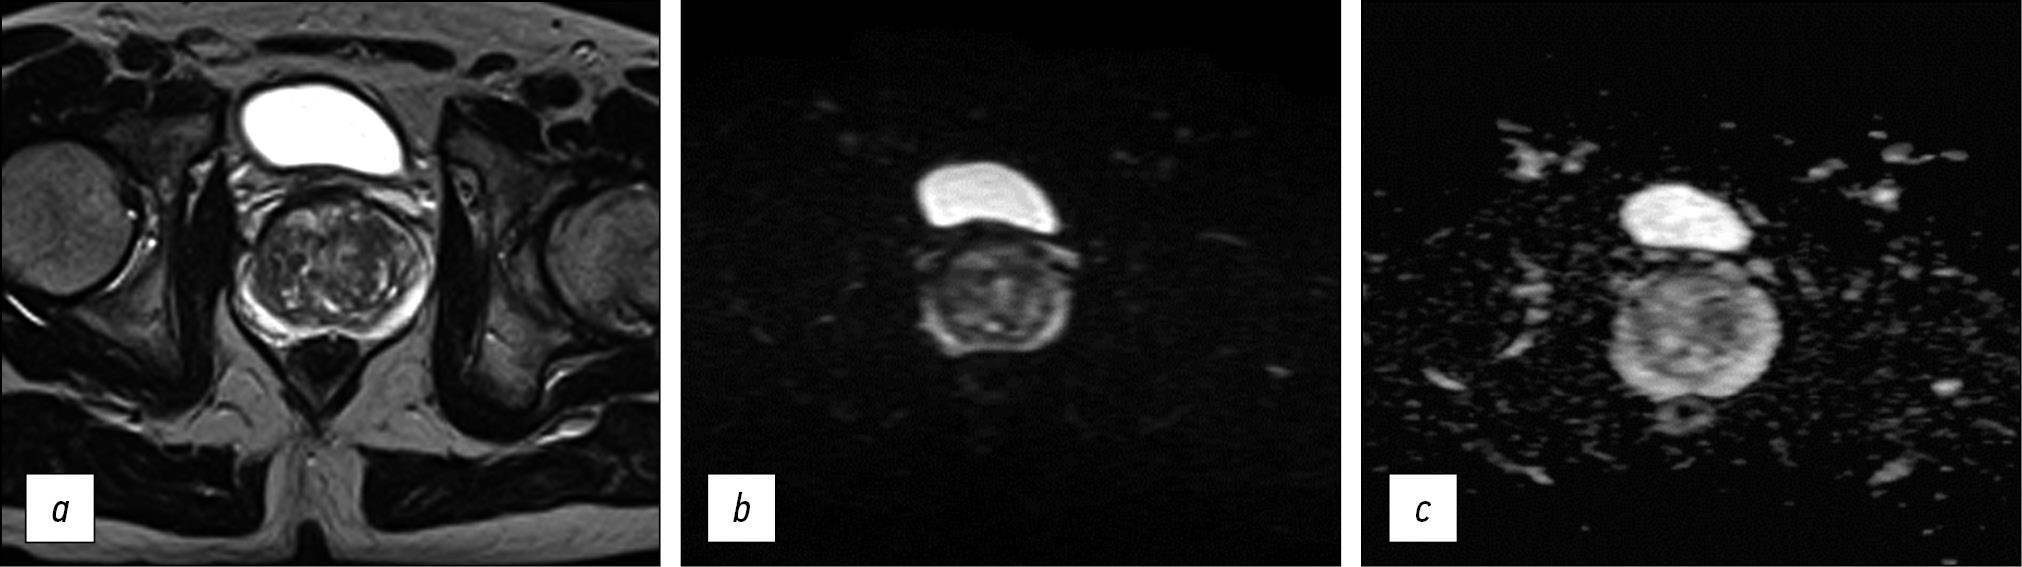

Fig. 2. Medical organization 1 (MO 1): a) T2-WI, axial projection (TR 5851, TE 120, FOV 35×30 cm, Matrix 256×256); b, c) DWI and ICD (TR 6772, TE 80, FOV 40×32 cm, Matrix 128×128).

Note. Here and in Figures 3–5: T2-WI, T2 weighted images; DWI, diffusion-weighted images; MDC, measured diffusion coefficient; TR, repetition time; TE, echo time; FOV, field of view; Matrix is a matrix.

Thus, in all presented HO MHD, the requirements recommended by PI-RADS v2.1 for the presence of T2-WI in the axial and at least one additional (sagittal and/or coronal) views were met. In addition, it should be noted that the recommended layer thickness for T2-WI in the axial view should be no more than 3 mm, while in HO 2 and HO 3, it is 4 mm (Figures 3 and 4). The same is true for HO 1, where the DWI slice thickness is 5 mm with the recommended 4 mm or less (Figure 2). An important factor is the field of view; according to PI-RADS v2.1, field of view (FOV) values for T2-WI should be 12–20 cm, while in HO 1 and HO 3, the field of view is much larger (30 × 35 cm and 40 × 30 cm, respectively) (Figures 2 and 4). According to PI-RADS v2.1, the recommended field of view for DWI is 16–22 cm, although none of the three HOs adhere to this standard. The fact of the variability of the FOV values and the section slice thickness inevitably affects the resolution and, as a result, the ability to detect lesions.